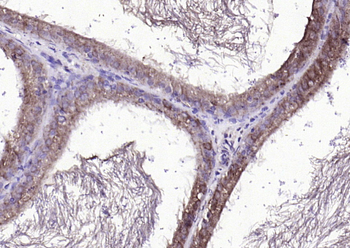

产品细节图片1

paraffin embedded (human prostate), Antigen retrieval by boiling in sodium citrate buffer (pH6.0) for 15 min, Block endogenous peroxidase by 3% hydrogen peroxide for 20 minutes, Blocking buffer (normal goat serum) at 37°C for 30 min, Antibody incubation with (FGF8) Polyclonal Antibody, Unconjugated (orb10653) at 1:200 overnight at 4°C, followed by operating according to SP Kit (Rabbit) instructionsand DAB staining.